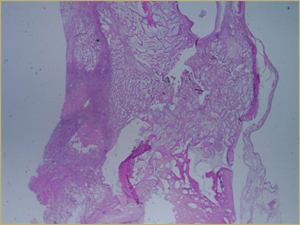

Sections from rabbits that received bioimplants containing DBM in a poloxamer carrier had residual particles of implanted allograft (Fig. 4a). These particles were larger than those of the autograft. None of the lacunae within the allograft were occupied by osteocytes (Fig. 4b). The margins of the implanted allograft also demonstrated active bone turnover and remodelling. As with the autograft, new bony regenerate was present within resorbed regions of the allograft, as well as between allograft particles.

Figure 4a: Low-power histologic examination of rabbit maxillary sinus augmented with demineralized bone matrix at 2 weeks after procedure. H&E stain, 50× magnification.